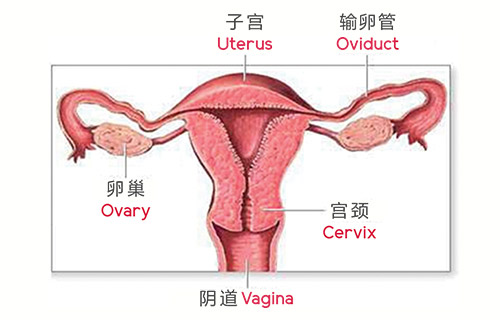

phoenixcareprincipletitle

- phoenixcareprinciple1

- phoenixcareprinciple2

- phoenixcareprinciple3

- phoenixcareprinciple4

- phoenixcareprinciple5

- phoenixcareprinciple6